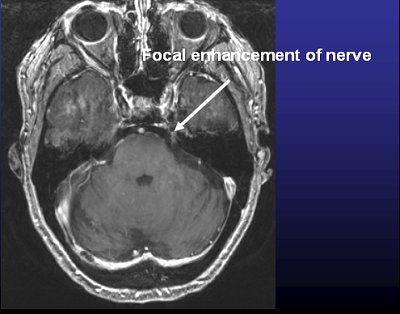

However, Erbay said that he believes visible TN markers do exist, and he's currently engaged in an ongoing trial to confirm TN with MRI. Erbay and colleagues published some early results of their work last year and found that trigeminal nerve atrophy can be depicted noninvasively with gadolinium-enhanced MRI (Radiology, February 2006, Vol. 238:2, pp. 689-692).

Except for ruling out dental problems and tumors, imaging has little value in TN assessment, according to the experts. That's mostly because there's generally nothing abnormal (deformation, inflammation) to see on imaging (Radiology, September 1989, Vol. 172:3, pp. 767-770; American Journal of Roentgenology, December 1994, Vol. 163:6, pp. 1447-1452).

Even the most sophisticated imaging exam can't necessarily distinguish between normal and abnormal vessel-nerve contact, according to Dr. Sami Erbay, a neuroradiologist at Lahey Clinic in Burlington, MA, and Tufts-New England Medical Center in Boston.

"The vessel and the nerve can be close to each other and contacting in normal people as well," Erbay said. "That makes it difficult for the imagers to see which one is an innocent contact, and which one is more severe neurovascular compression leading to trigeminal neuralgia."